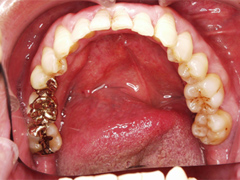

1.接着ブリッジ

健康な歯を削る量を最大限に抑え、接着ブリッジを行なう

写真(1)